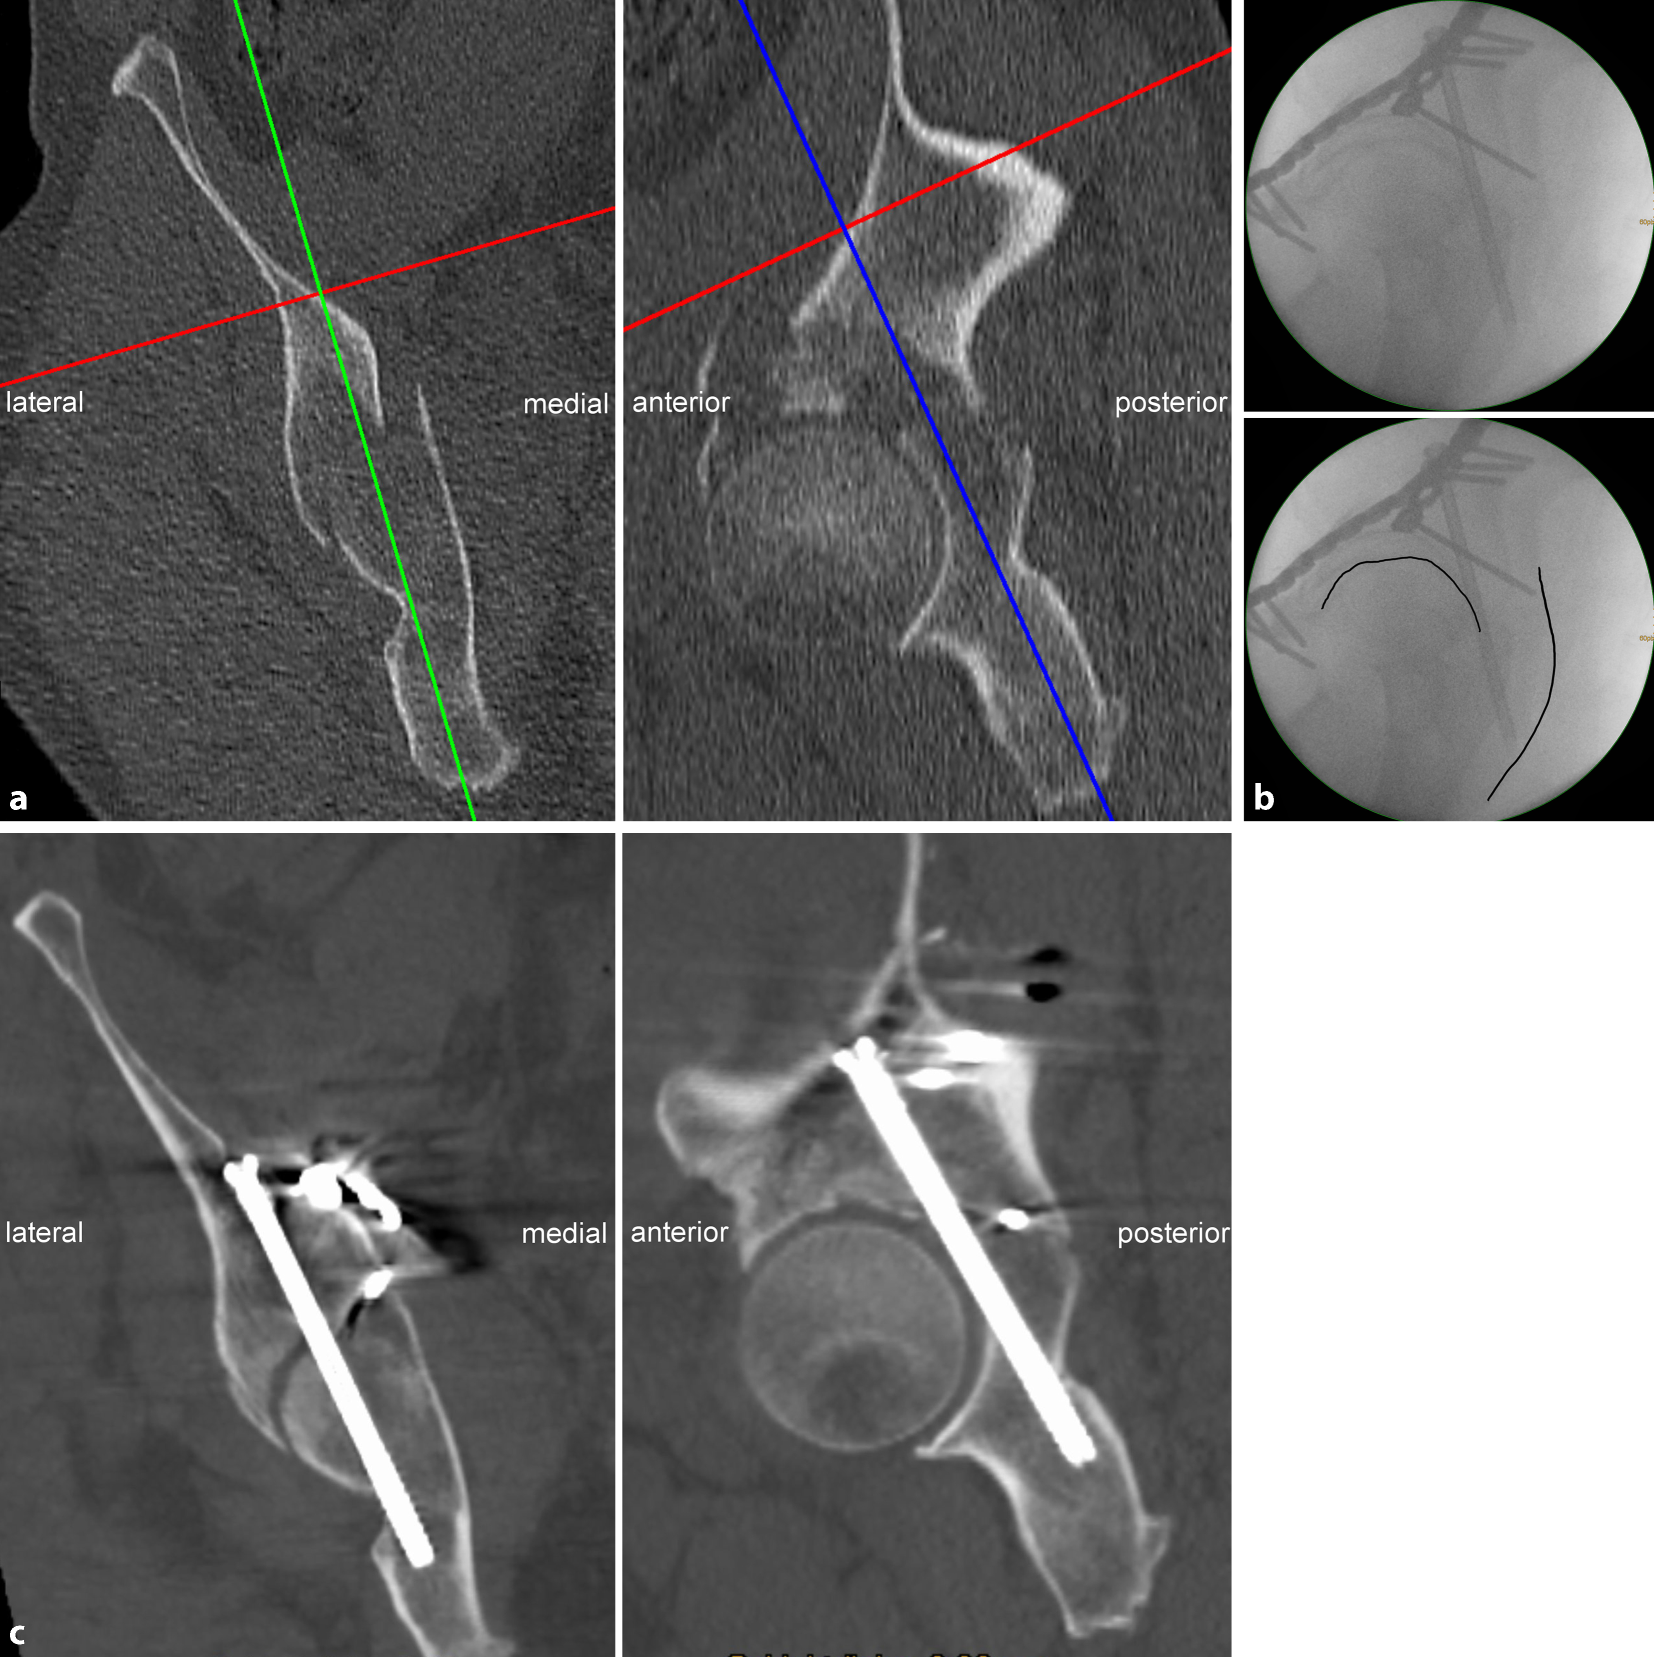

• Screw misplacement: revision surgery in the case of neurological impairment or intraarticular screw penetration (Fig. 7)

Fig. 7

Screw misplacement. a Preoperative planning for a 56-year-old man who sustained a typical anterior column with posterior hemitransverse fracture (ACPHF) on the right side. The preoperative planning reveals a relatively narrow osseous corridor for a posterior column screw. b Fluoroscopic control in lateral–oblique view. The image quality is moderate in general. Additionally, the lateral–oblique view was not sufficiently oblique resulting in a poor differentiation between the left and the right hip and sciatic tuber (upper image). The screw does not perforate the cortical bone at the sciatic tuber, but is tangent to the projection of the hip joint line (lower image). c Postoperative CT scans revealed adequate reduction of the posterior hemitransverse fracture via the quadrilateral plate. The posterior column screw, however, penetrates the cortex of the acetabular fossa. The hip joint motion was not restricted and the patient refused revision surgery